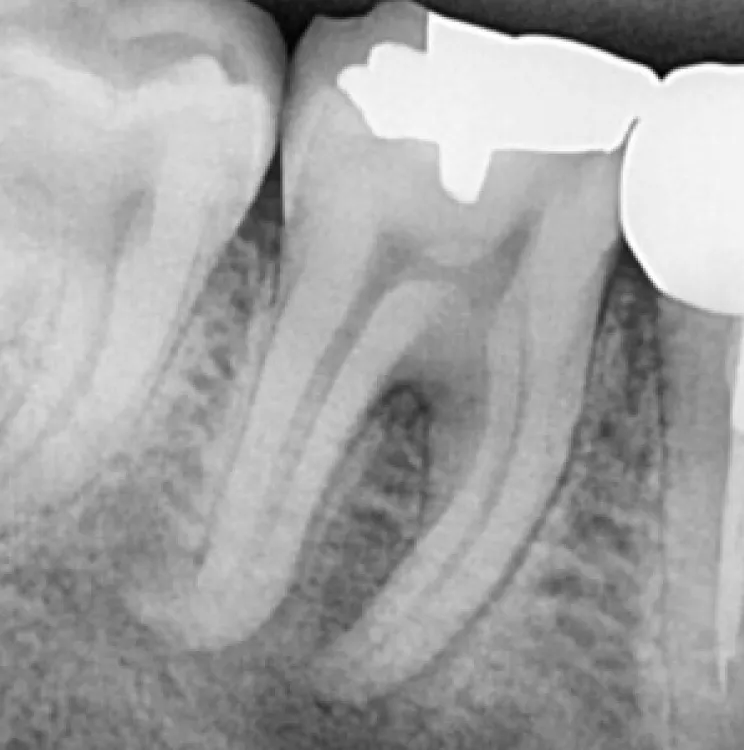

Résultats clinique

1

Avant le traitement

2

Après le traitement